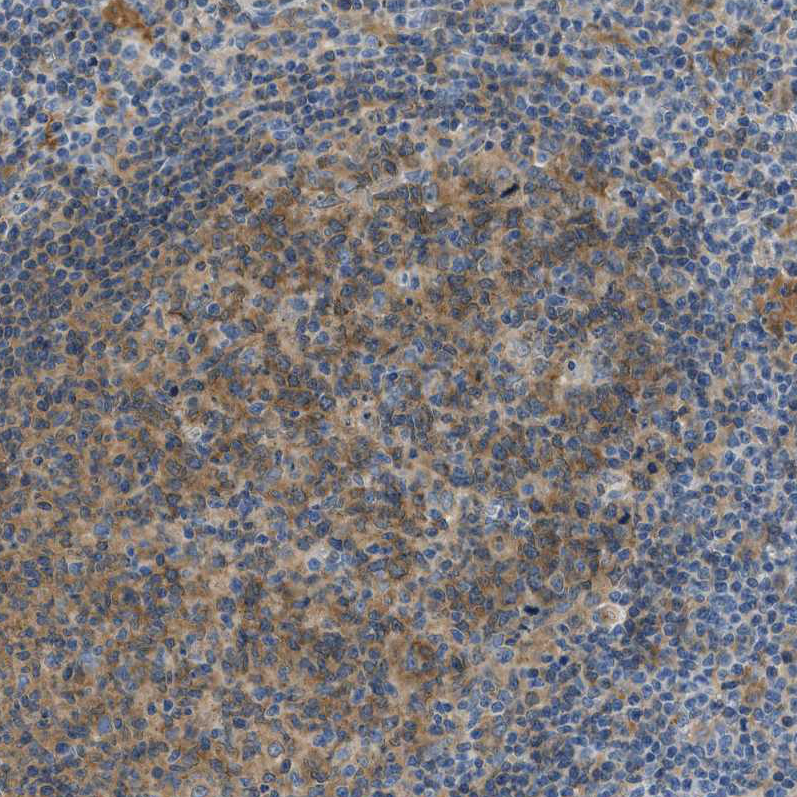

Immunohistochemical staining of human urinary bladder shows moderate to strong cytoplasmic / membranous positivity in urothelial cells.